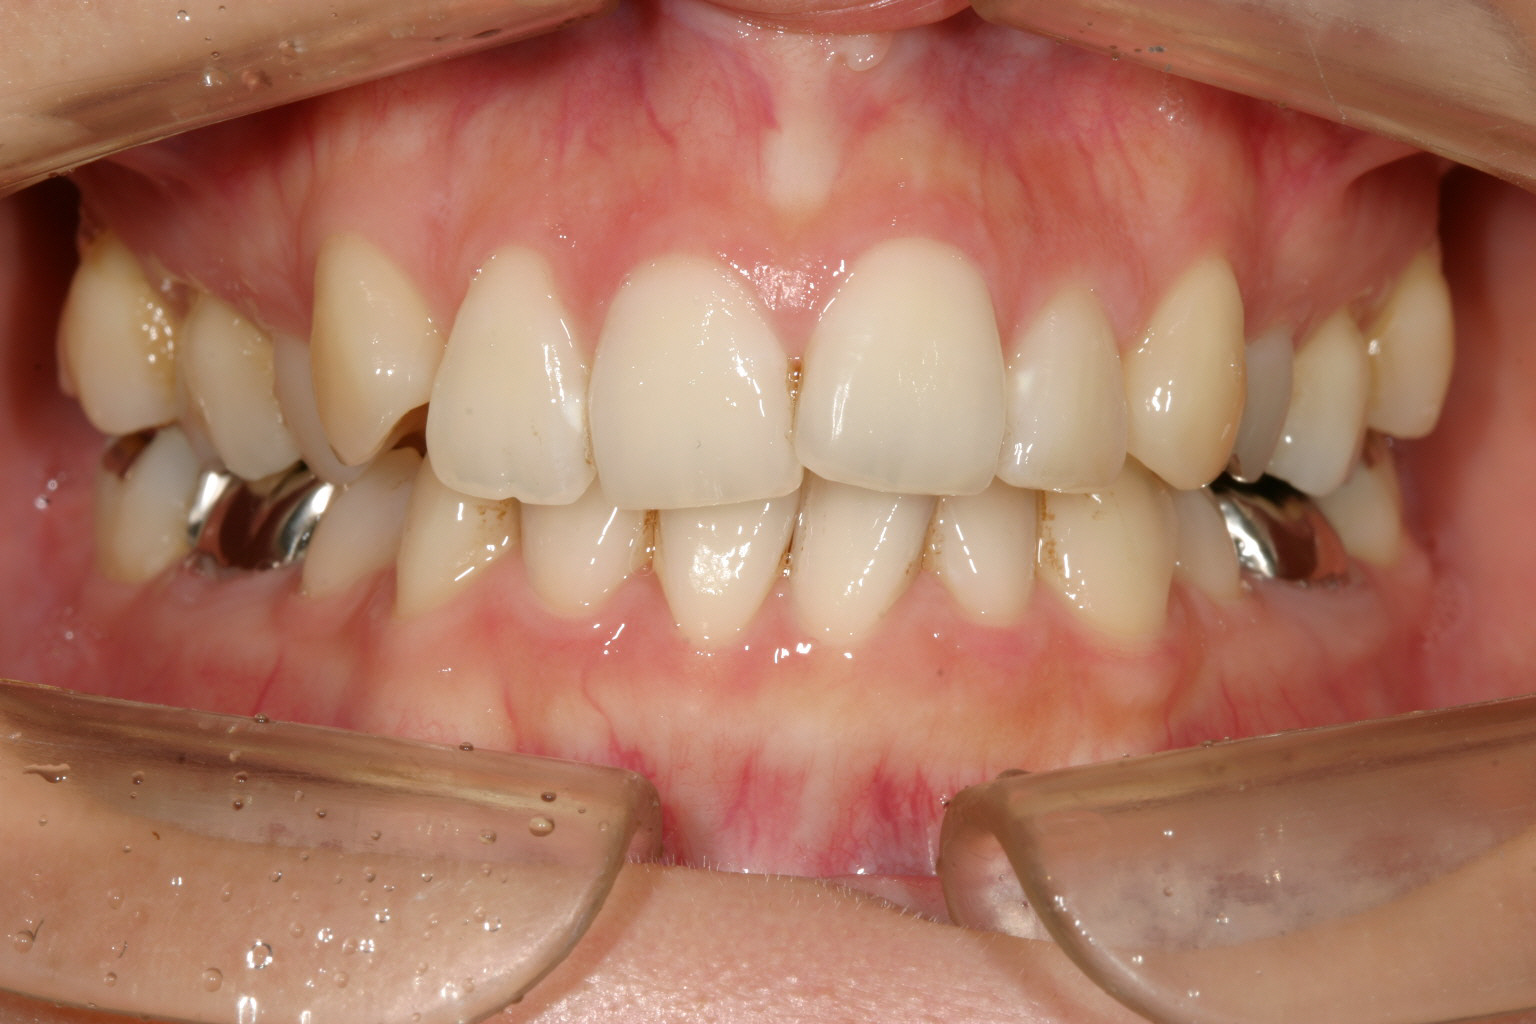

以前に矯正治療されたらしいですが後戻りしています、

下顎も叢生が出てきています。

少し上顎出ていますね~

特に上顎のアーチが狭くなり先が尖って、それに合わせて下顎も叢生が再発していました。